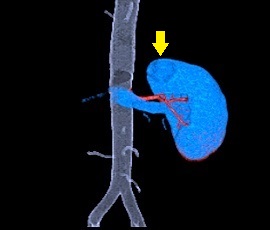

腎ダイナミックCT(3D)画像